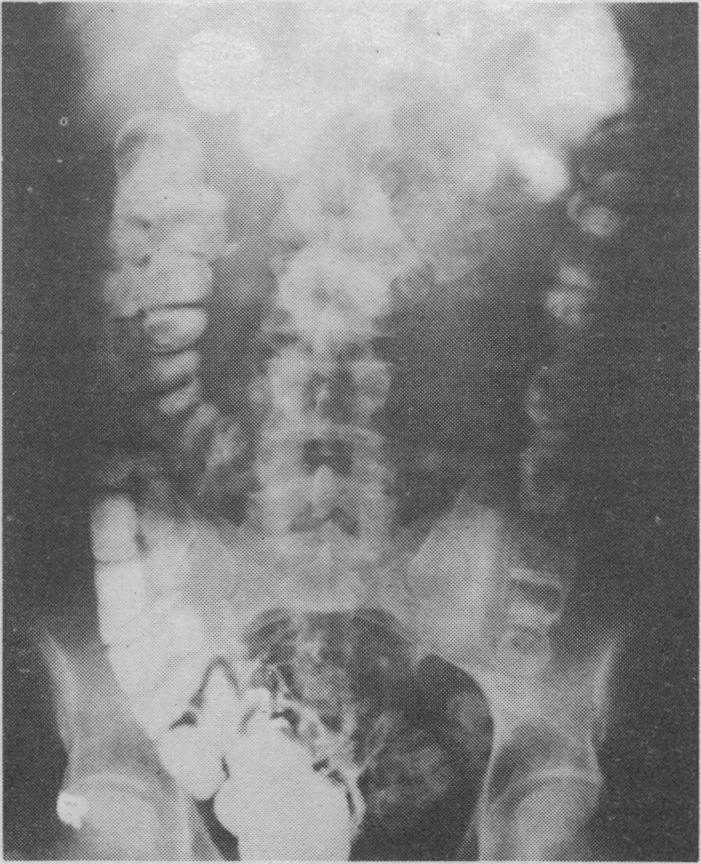

Bauer F

Br Med J. 1970 Jan 10;1(5688):111-2. doi: 10.1136/bmj.1.5688.111-b.